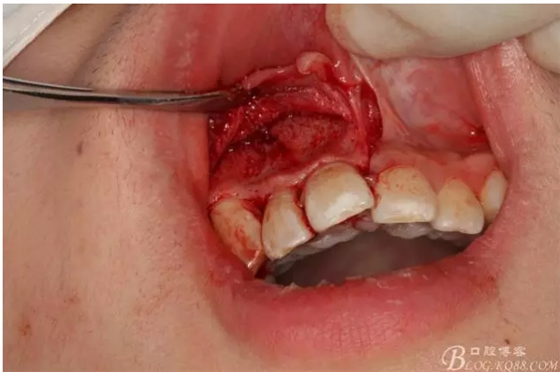

圖2.根管治療術后直接局部 麻醉下切開、翻瓣,發(fā)現(xiàn)12唇側骨壁有綠豆大小骨缺損

圖3.依缺損部位為中心,逐漸去骨,完整暴露出囊壁。